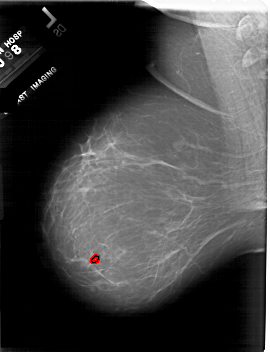

A_1818_1.LEFT_CC

LEFT_CC LINES 6766 PIXELS_PER_LINE 4726 BITS_PER_PIXEL 12 RESOLUTION 43.5 OVERLAY

FILE: A_1818_1.LEFT_CC.OVERLAY

TOTAL_ABNORMALITIES 1

ABNORMALITY 1

LESION_TYPE CALCIFICATION TYPE PLEOMORPHIC DISTRIBUTION CLUSTERED

ASSESSMENT 4

SUBTLETY 1

PATHOLOGY BENIGN

TOTAL_OUTLINES 1

BOUNDARY